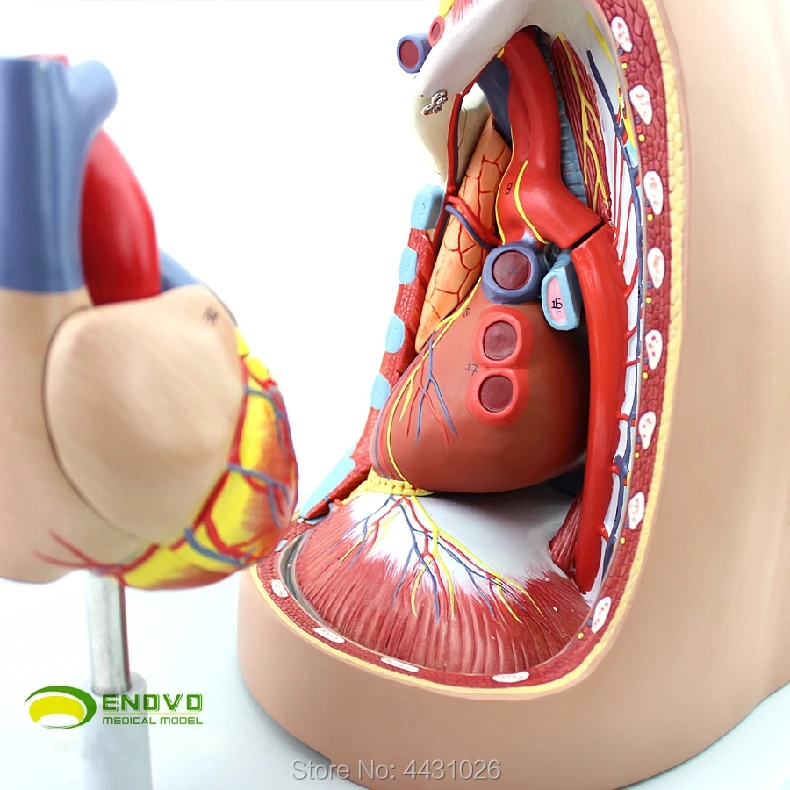

Фотографии и 3D-модели анатомии сердца человека